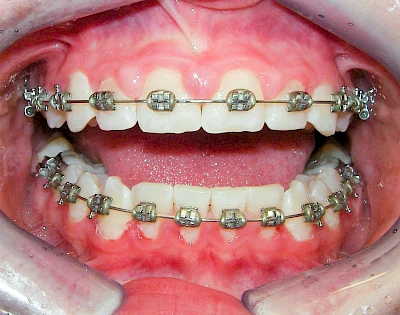

Bakterien in den Zahnbelägen greifen neben den Zähnen auch das Zahnfleisch (Gingiva) und den gesamten Zahnhalteapparat (Parodont) an. Der Körper reagiert mit einer Entzündung, sichtbar als Rötung und Schwellung. Meist blutet das Zahnfleisch z .B. beim Essen oder auch beim Putzen der Zähne.

Ist zunächst nur das Zahnfleisch von der Entzündung betroffen, spricht man von Gingivitis. Später, wenn auch der Knochen um die Zähne herum entzündet ist, spricht man von einer Parodontitis. Bei der Parodontitis wird der Knochen nach und nach abgebaut und das Zahnfleisch zieht sich zurück. Die Zahnhälse und Zahnwurzeloberflächen liegen mehr und mehr frei. Die Zähne werden zunehmend lockerer und fallen schließlich aus.